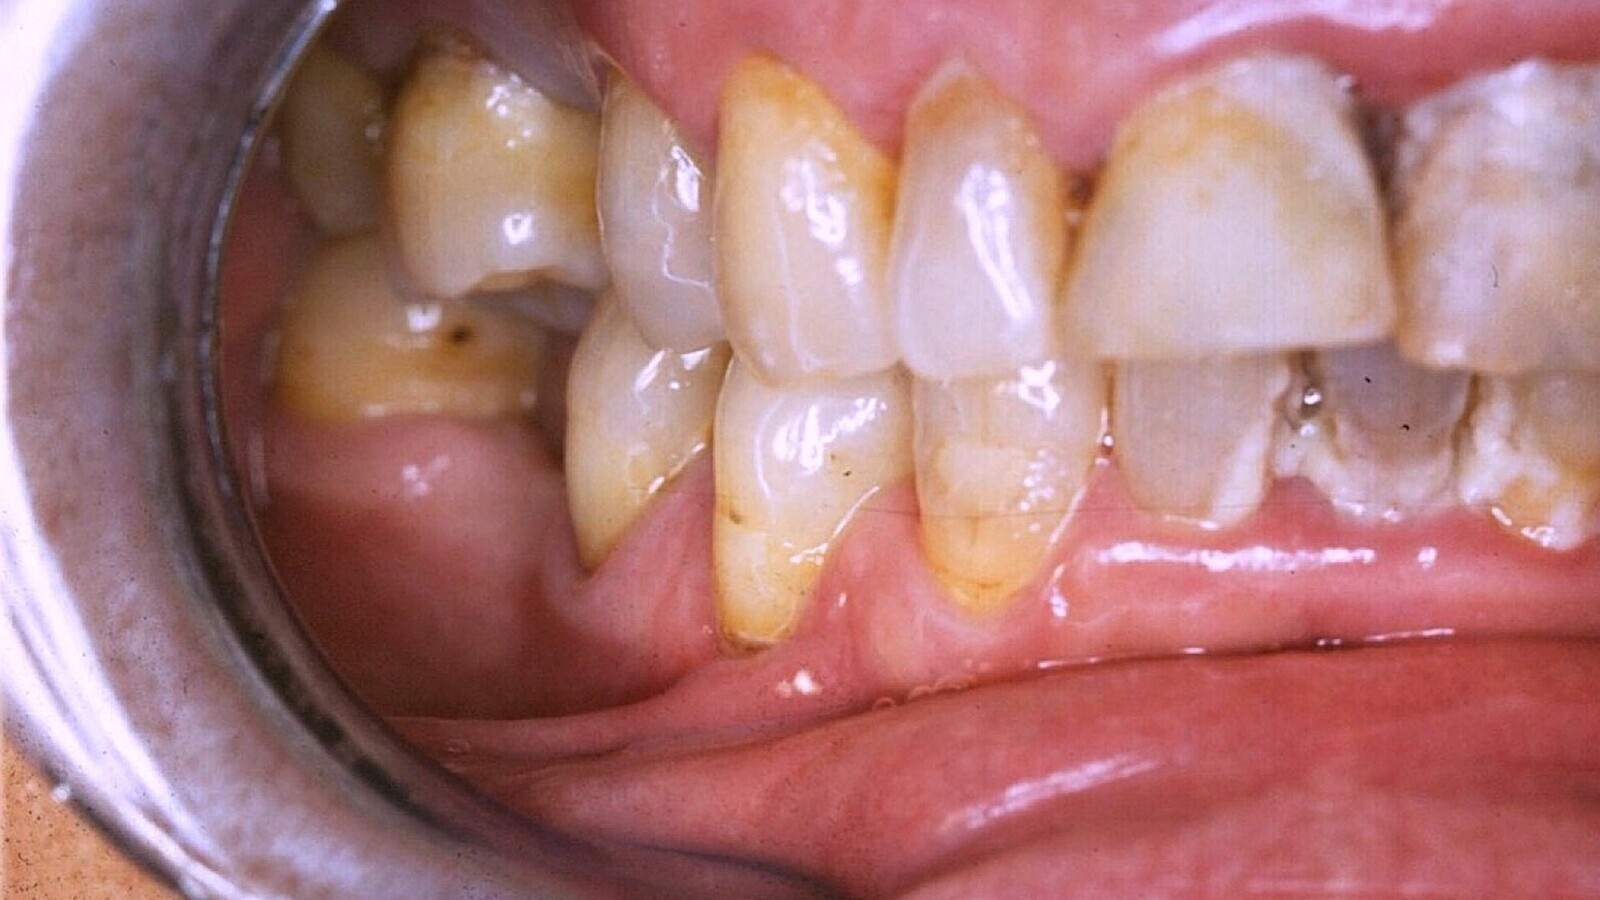

Una vez revisados por el odontólogo y realizado el diagnóstico de sus necesidades, se le realizarán los tratamientos necesarios (empezando por la higiene-detartraje y/o raspados, extracciones de dientes no recuperables y tratamientos de caries si las hubiera). Posteriormente, el odontólogo valorará al paciente en función del “riesgo percibido” para poder incluirlo en un protocolo de mantenimiento, programando así las visitas futuras, con una frecuencia que dependerá de su situación de salud general (Figs. 2, 3 y 4).

Figura 3. Paciente con riesgo moderado de caries, higiene deficiente, ausencia de dientes y obturaciones (historia de caries). En casos de riesgo moderado de caries se aconseja realizar revisiones cada 3 a 4 meses.

Figura 4. Paciente de alto riesgo, con ausencias dentales, portador de prótesis removible, obturaciones, caries activas y presencia de placa. En casos de alto riesgo se deben realizar los tratamientos pertinentes y las revisiones cada 2 a 3 meses.

Una vez que el paciente se cataloga de bajo, medio o alto riesgo de desarrollar problemas bucodentales (acumulo de placa, caries radiculares), se le incluirá en un programa. El consejo es realizar visitas inicialmente cada 2 meses en aquellos pacientes de alto riesgo y como máximo cada 6 meses en los de bajo riesgo. En cada una de las visitas, el odontólogo hace una revisión, si hay que realizarle algún tratamiento y valoración de su evolución, y el/la higienista dental procede a realizarle una limpieza nuevamente y aplicar el barniz o gel fluorados que le indique el odontólogo (Figs. 5, 6 y 7). Posteriormente, se reforzarán las instrucciones para la limpieza diaria por el propio paciente, personal auxiliar cuidador o familiares del paciente.